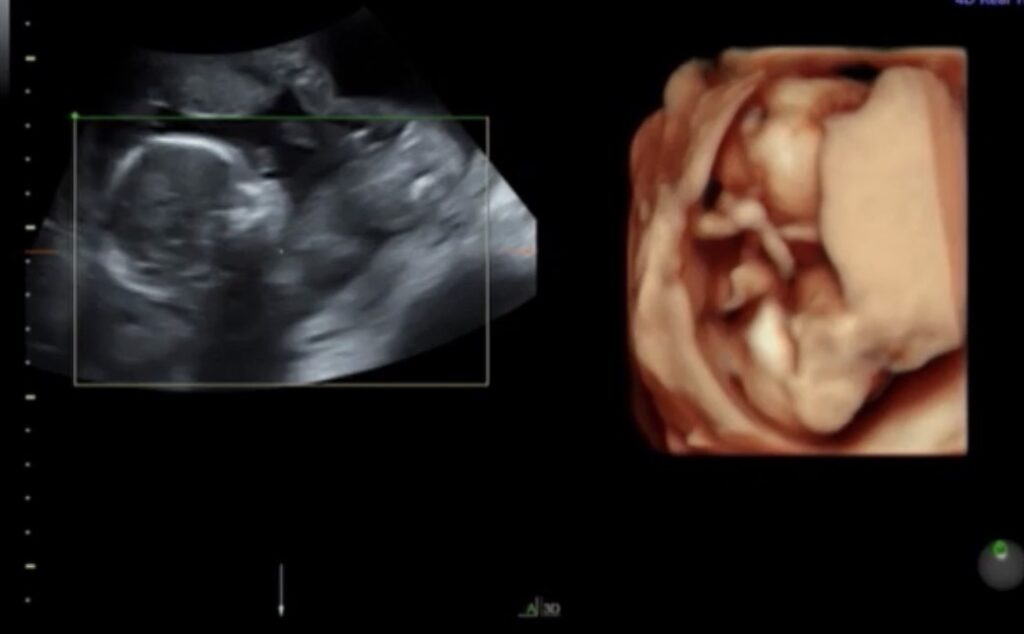

③18w0d|「あれ?女の子?」逆転の瞬間

ここでまさかの展開が起きます。

3回目の判定は18w0d。

それまで7割男児と言われていたのに、ここでまさかの7割女児という結果に変わりました。

↑この時点のエコーがこちらです。ここで女児判定に変わりました。